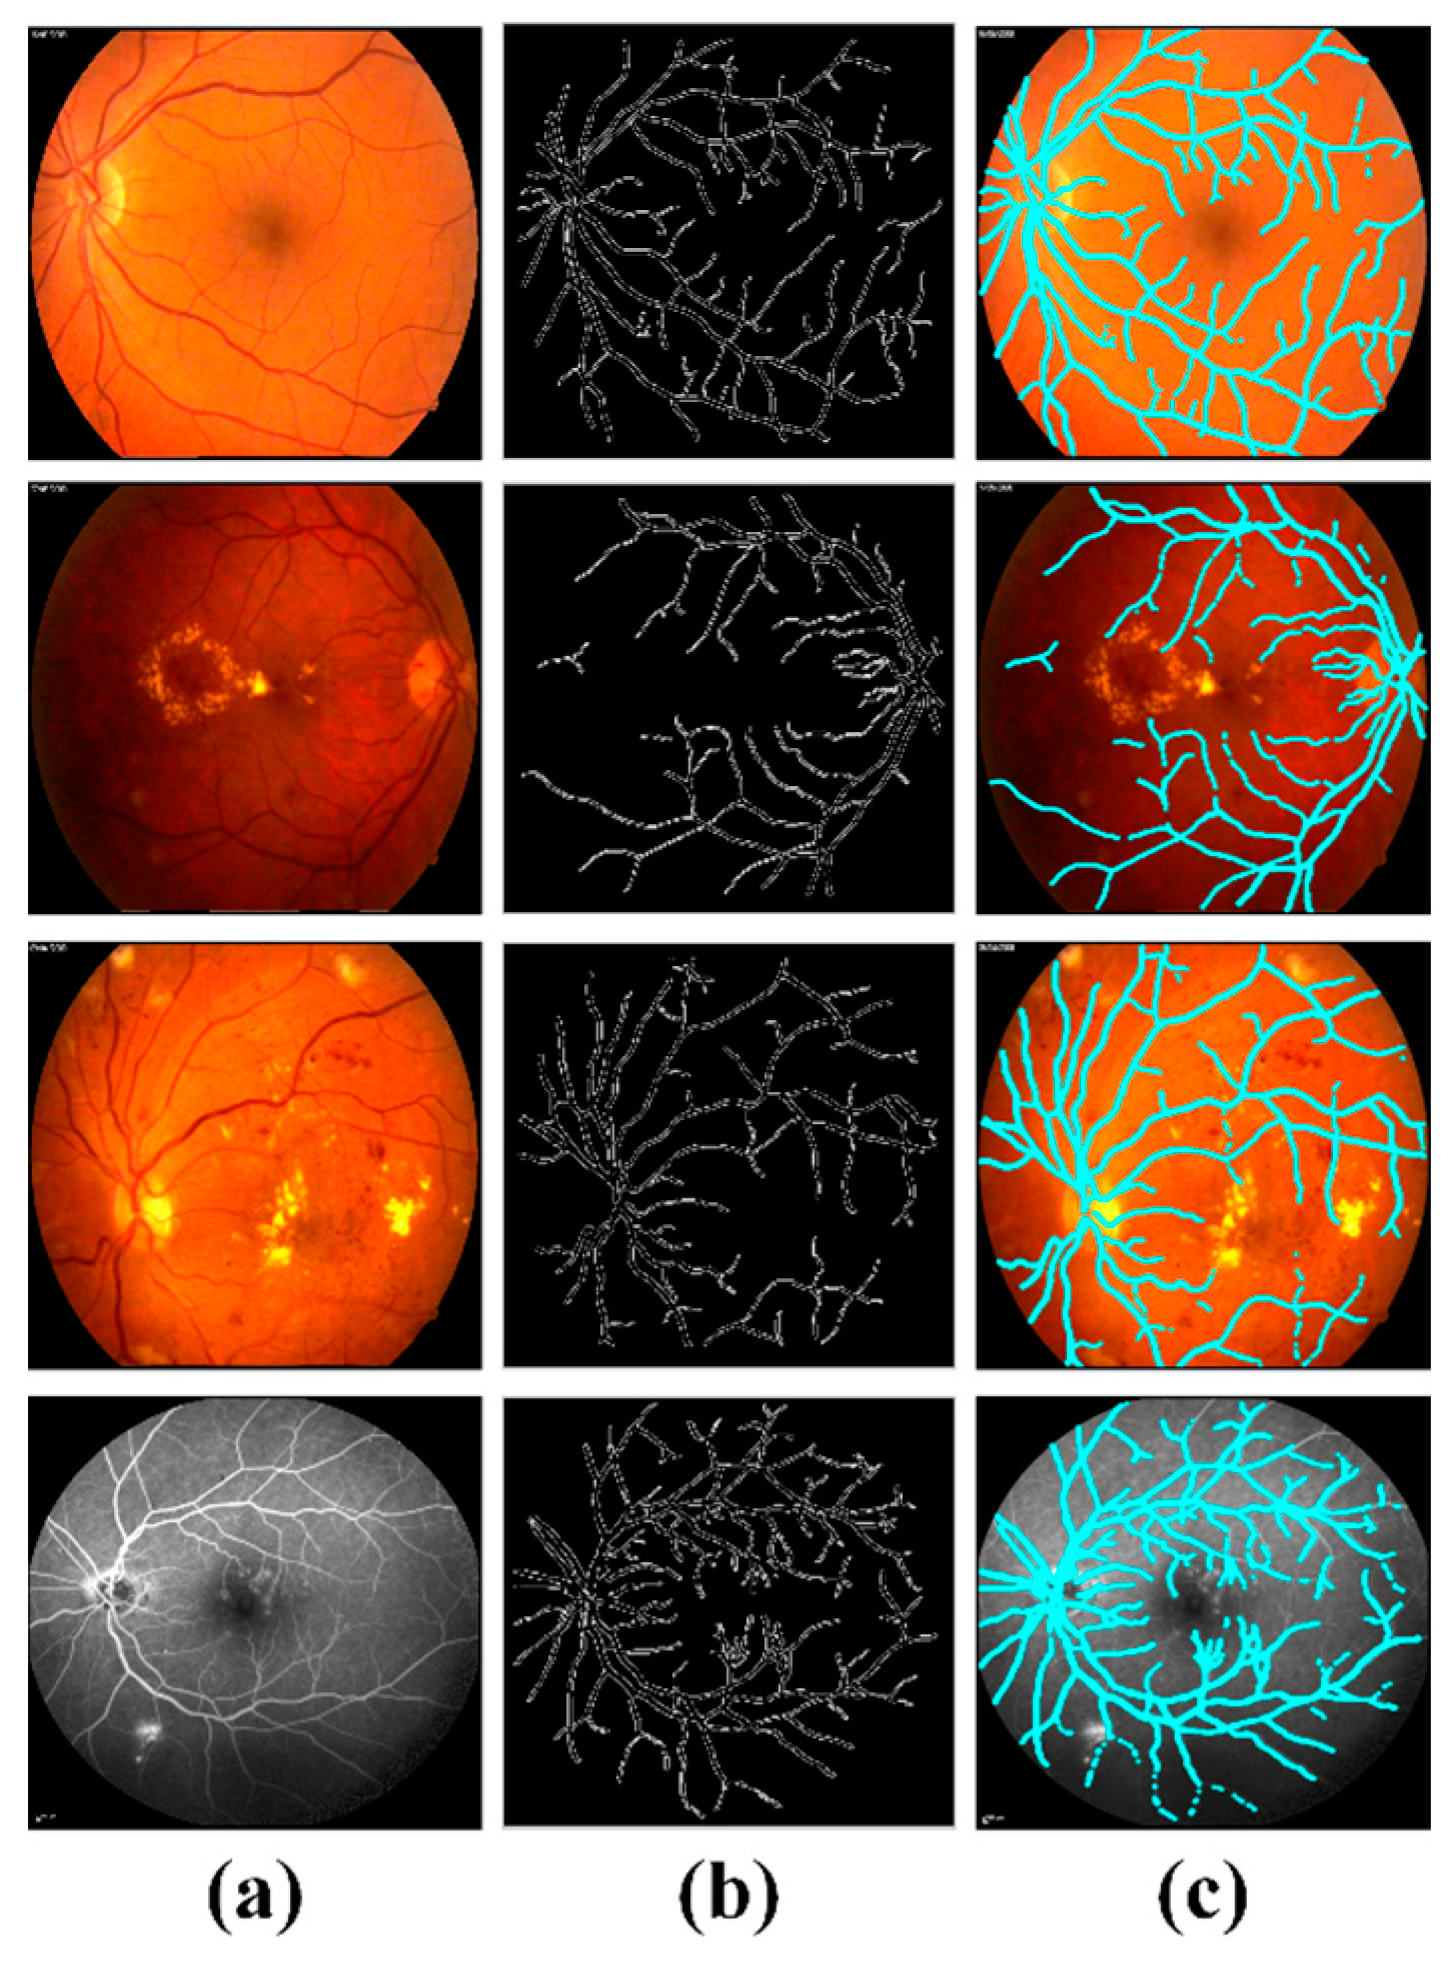

4.3. Extraction of Clinically Significant ME Pathological Symptoms